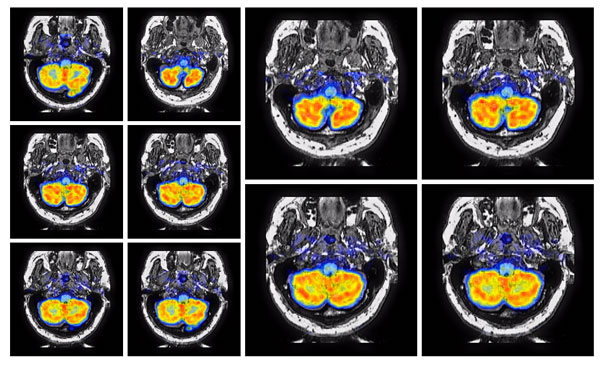

Investigation of deep learning image fusion techniques for medical imaging

Angayarkanni Veeraputhiran, Muthukumar Balamurugan and Varun P. Gopi

pp. 347 - 354 PDF PDF w/Links